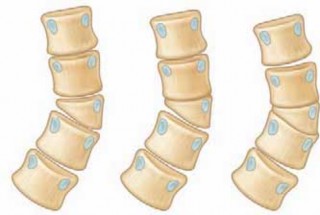

Chapter 63 Hemivertebra Excision Daniel J. Hedequist and John B. Emans DEFINITION A hemivertebra is a congeni…